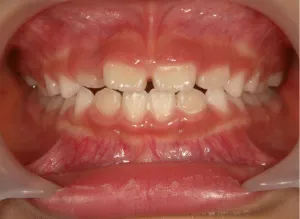

治療前①小1(7y2m):初診

*上顎前歯後方傾斜、上下唇の突出、口唇閉鎖不全傾向、コンケーブなし

| カウンセリング・診断結果 | 骨格的に下顎前方位で下顎骨も大きいタイプで、上の前歯が後ろに傾斜している受け口です。 顔立ちは上下唇が突出していて口唇閉鎖不全傾向がありますが、コンケーブにはなっていません(写真①)。 機能的に低位舌があり、今後受け口を助長する可能性があります。 受け口は、上顎骨の骨格的な前方向の成長を阻害し下顎が前へ強く成長していくため、骨格的な受け口が悪化し永久歯の咬合治療が難しくなり、症例によっては外科的な治療が必要になることがあるため早期に改善し骨格的な悪化を予防する説明をしました。 |